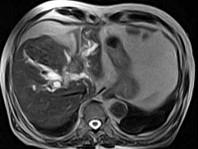

问题 男,43岁,右上腹痛,黄疸,AFP阴性,消瘦乏力,影像检查如下图,诊断为()

选项 A.急性化脓性胆管炎 B.胆管癌 C.脂肪肝 D.原发性肝癌 E.肝血管瘤

答案 B